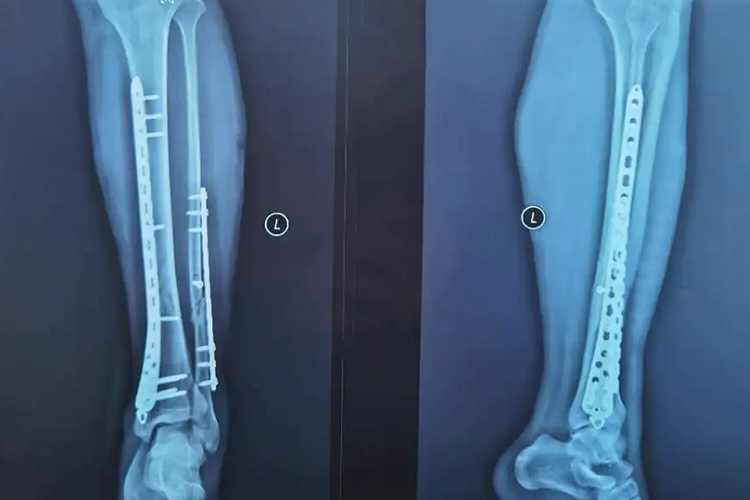

小腿骨折钢板一般适用于手法复位难以整复,以及合并血管、神经损伤等骨折的固定。小腿不同部位的骨折,钢板所置位置不同。胫骨干中段骨折,可以将钢板置于胫骨外侧面。胫骨干近段、远段的骨折,可以将钢板置于胫骨外侧面。对于胫骨内侧有开放伤口的患者,将钢板置于胫骨外侧、胫前肌肉覆盖内固定物,避免伤口感染、皮肤坏死等造成内固定物外露,对于胫骨前方软组织广泛损伤的患者,也可以转移肌皮瓣覆盖内固定物。